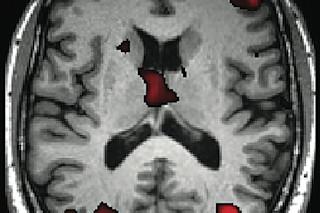

An MRI scan of Duncan’s brain highlights areas (in red) that screen out irrelevant information—a process that weakens as we age.

A functional MRI scan measures blood flow in Duncan’s brain while he challenges his memory. Colored areas show his motor cortex activating as he responds to a test by clicking a mouse.